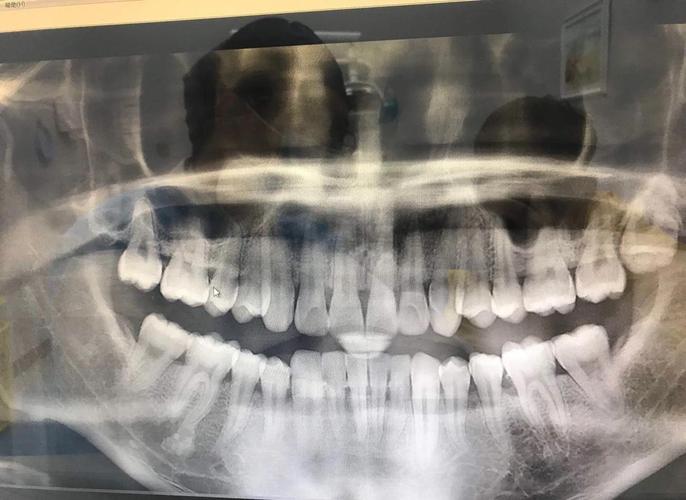

全景片(曲面断层片)

全景片是矫正牙齿最基础的检查,可一次性显示全口牙齿、牙槽骨、颌骨及周围重要解剖结构(如上颌窦、下颌神经管),其主要作用包括:

- 牙齿发育情况:观察牙齿数量(是否存在多生牙、缺失牙)、形态(如过小牙、锥形牙)、位置(如牙齿是否萌出、阻生)及牙根形态(有无弯曲、吸收)。

- 牙槽骨状况:评估牙槽骨高度、密度,是否存在骨缺损、囊肿或肿瘤等病变。

- 颌骨关系:初步判断上下颌骨的位置关系,如下颌是否偏斜、颞下颌关节是否有异常(如髁突形态改变)。

- 第三磨牙情况:判断智齿位置、方向及对相邻牙齿的影响,尤其是对需要拔牙矫正的患者,可提前规划拔牙方案。

注意事项:全景片为二维影像,存在重叠干扰,对细小结构(如牙根吸收、邻面龋)的分辨率有限,需结合其他检查补充。